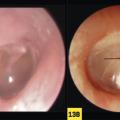

Carcinome épidermoïde de l'oreille

CARCINOME EPIDERMOIDE